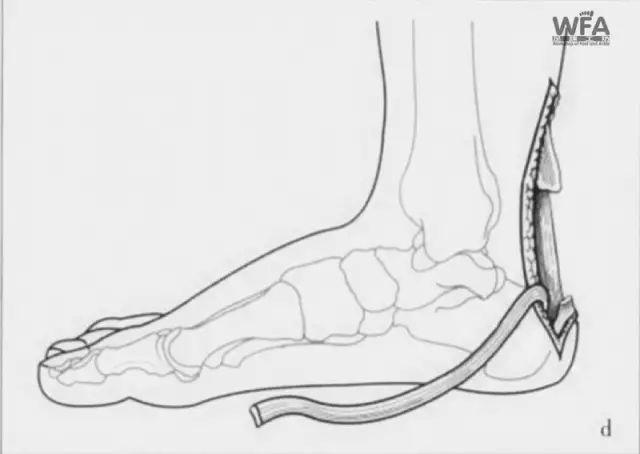

手术示意图

为了尽量规避以上问题,骨伤中心副主任许锦涛决定采用目前较有优势的微创切取全长踇(拇)长屈肌腱重建陈旧性跟腱断裂术。

术中,医护团队精细操作,“用脚底的肌腱修复脚后跟肌腱”,即用踇(拇)长屈肌腱修补跟腱,稳定踝关节。患者术后功能康复后良好,手术圆满成功。

本术式具有术后恢复快、肌腱固定强度高、并发症少的优势,不仅适用于慢性跟腱断裂缺损较大的患者,还适用于因慢性跟腱广泛病变,而需切除较大范围病变跟腱的患者,但不适用于对踇(拇)趾有较高要求的职业运动员和运动爱好者。

其中微创切取全长踇(拇)长屈肌腱重建陈旧性跟腱断裂术使用的踇(拇)长屈肌腱具有肌腱长、韧性好、肌力强、收缩力轴与跟腱类似等优点,有利于保持踝关节肌力平衡,常切取后用来修复跟腱、腓骨肌腱、胫后肌腱,手术具有安全可靠、疗效确切等优点,广受患者好评!